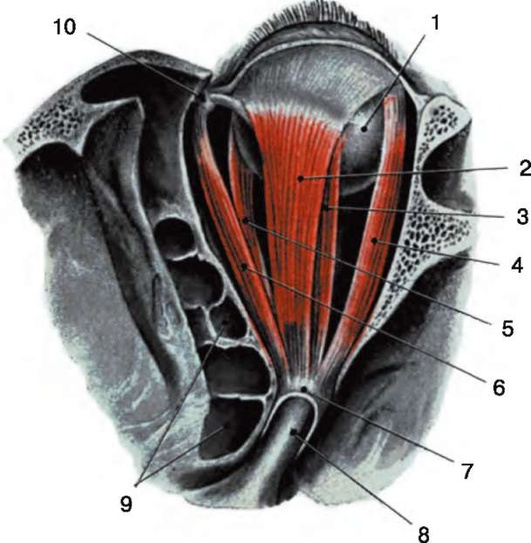

Рис. 3.3. Наружные мышцы глаза: 1 - глазное яблоко; 2 - мышца, поднимающая верхнее веко; 3 - верхняя прямая мышца; 4 - латеральная прямая мышца; 5 - медиальная прямая мышца; 6 - верхняя косая мышца; 7 - общее сухожильное кольцо; 8 - зрительный нерв; 9 - гайморова полость; 10 - лобная пазуха